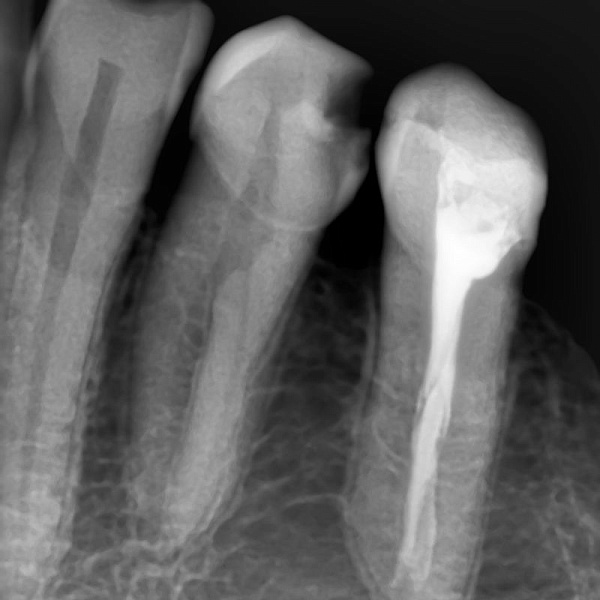

- Высококачественные снимки

- Высокая чувствительность для лучшего качества и низкая доза излучения